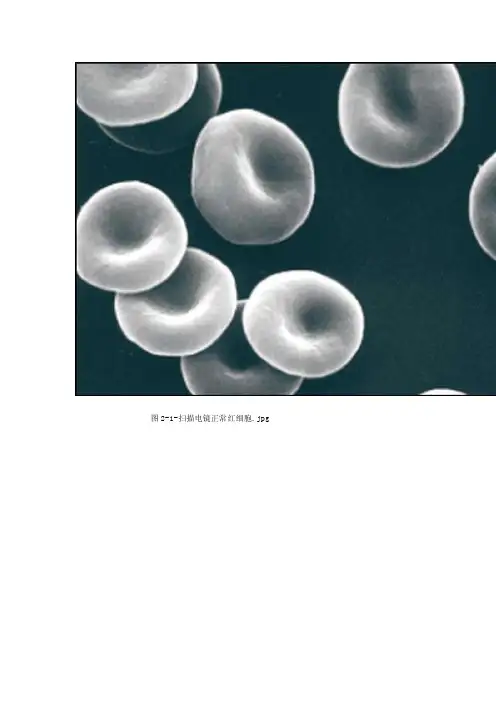

【参考值】正常红细胞呈双凹圆盘状,细胞大小较一致,直径范围6~9μm,平均直径为μm,中央1/3为生理性中央淡染区,胞质内无异常结构。

图2-1-扫描电镜正常红细胞.jpg图2-2-缗钱状.jpg图2-3-嗜多色.jpg图2-4-嗜碱性点彩红细胞.jpg图2-5-染色质小体.jpg图2-6-卡波环.jpg图2-7-有核红细胞.jpg图2-8-血细胞比容结果判断.jpg图2-9-网织红细胞.jpg图2-10-Miller窥盘结构示意图.jpg图2-11-正常红细胞.jpg图2-12-中性粒细胞类白血病.jpg图2-13-嗜酸粒细胞类白血病.jpg图2-14-正常五种白细胞.jpg图2-15-中性杆状核.jpg图2-16-中性粒细胞分叶核.jpg图2-17-中性粒细胞大小不均.jpg图2-18-中毒颗粒.jpg图2-19-红细胞大小不均.jpg图2-20-空泡形成.jpg图2-21-杜勒小体.jpg图2-22-中性粒细胞退行性变.jpg图2-23-棒状小体.jpg图2-24-中性粒细胞的核象变化.jpg图2-25-中性粒细胞核左移.jpg图2-26-中性粒细胞核右移.jpg图2-27-巨红.jpg图2-28-异型淋巴1.jpg图2-29-异型淋巴Ⅱ.jpg图2-30-异型淋巴Ⅲ.jpg图2-31-卫星核淋巴细胞.jpg图2-32-球形红.jpg图2-33-正常血小板.jpg图2-34-大血小板.jpg图2-35-异常形态血小板.jpg图2-36-血小板聚集.jpg图2-37-PT检测原理.jpg图2-38-APTT检测原理.jpg图2-39-椭圆红细胞.jpg图2-40-靶红.jpg图2-41-棘形红.jpg图2-42-泪滴形红细胞.jpg。